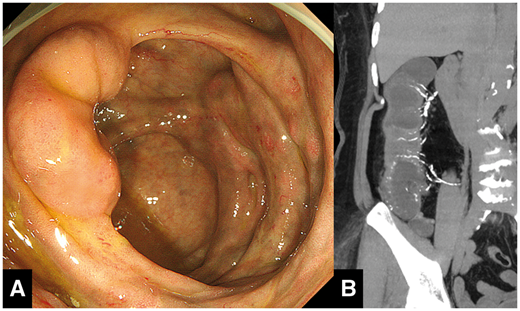

「Idiopathic mesenteric phlebosclerosis」は本邦で初めて報告され、近年疾患概念が確立した非常に特徴的な所見を有する消化管疾患です。日本語では「特発性腸間膜静脈硬化症」と呼ばれます。

症状としては長期にわたる腹痛や血便があり、回盲部から横行結腸にかけて大腸内視鏡所見で大腸粘膜が深青色、黒紫色に変化し、粘膜の菲薄化や潰瘍などが認められます。またCTでは腸間膜静脈の著明な石灰化が描出されます。

これらの原因は長らく不明であったのですが、現在では漢方薬の長期内服が発症要因であることが判明しています。原因となる漢方薬の成分は山梔子(サンシシ)であり、サンシシが有するゲニピンが回盲部で吸収される際に腸内細菌の働きで着色、さらに吸収される際に腸間膜静脈に沈着して長期間にわたり炎症を引き起こすことから石灰化を生じ、慢性的な腸管虚血を引き起こすものとされています。大抵は漢方薬内服中止で軽快しますが、一部では改善が認められず外科的切除を必要とする症例もあるそうです。

なお、ほとんどの症例は漢方製剤を使用可能な東アジアに偏っています(1例だけカナダからの報告があるものの患者は台湾からの移民)。